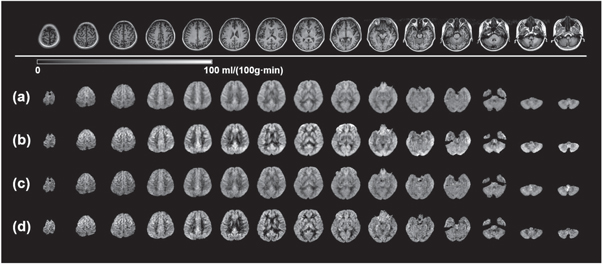

Each of the four volunteers underwent scans with four different acquisitions such that 16 datasets in total were collected. Figure 3 shows the CBF maps from the four data acquisitions for the 29 y/o male volunteer. 15 equidistant slices out of the full brain covering 32 slices are displayed as a representation. For the data with the regular resolution, the CBF maps with segmented kz acquisition (RR-S2, figure 3(b)) show more prominent GM/WM contrast in comparison to those with conjoint kz acquisition (RR-S1, figure 3(a)). Similarly, as comparing HR-S2 (figure 3(d)) and HR-S1 (figure 3(c)), this sharper GM/WM contrast can also be observed at a higher spatial resolution, although the high resolution maps (figures 3(c) and (d)) suffer relatively lower SNR. Regardless of whether or not the kz segmentation is employed, the low SNR in the high resolution images is a considerable issue and will be noted in the discussion section.

Figure 3. CBF maps of multi-delay ASL using four GRASE acquisition designs. The mapping results were acquired on a 29 y/o subject as a representation. 15 equidistant CBF maps out of total 32 slices are shown as a representation. Top row: T1 FSE FLAIR anatomical images for the same corresponding slices. With RR-S1(a), RR-S2(b), HR-S1(c), and HR-S2(d) acquisitions, variations of the CBF maps were resulted.

Standard image High-resolution imageThe ATT maps from the four datasets on the volunteer are shown in figure 4 for the same 15 slices as in figure 3. Similarly as what has been found in the CBF maps, not surprisingly, the regular spatial resolution ATT maps (figures 4(a) and (b)) present higher SNR than those with the high resolution (figures 4(c) and (d)). Notably however, this SNR loss is more significant compared to that of the CBF maps. The most remarkable difference in comparing these four sets of maps is that the ATT contrast among particular regions of the brain is much more pronounced in the GRASE acquisition with regular resolution and segmented kz (RR-S2, figure 4(b)). The contrast is interpreted in two perspectives. First if we look at tissues, WM generally exhibits longer ATT than GM. Second, occipital lobe and cerebellum in posterior circulation show longer ATT than frontal, parietal and temporal lobes in anterior circulation. This distinct contrast becomes obscure when utilizing conjoint kz GRASE acquisition (figure 4(a)). When high resolution acquisition is employed, SNR becomes an issue and this distinct contrast fades away (figure 4(d)). Further, if conjoint kz is used for the high resolution acquisition, an even more depressed contrast in obscure appearance is resulted (figure 4(c)).

Figure 4. ATT maps of multi-delay ASL using four GRASE acquisitions. The mapping results were acquired on the 29 y/o subject as a representation. 15 equidistant ATT maps out of total 32 slices are shown as a representation. Top row: T1 FSE FLAIR anatomical images for the same corresponding slices. With RR-S1(a), RR-S2(b), HR-S1(c), and HR-S2(d) acquisitions, variations of the ATT maps were resulted.

Standard image High-resolution imageTwo representative slices are selected from figures 3 and 4, and are displayed head-to-head in figure 5. In this enlarged comparison, the mapping characteristics mentioned above can be more clearly recognized. As for the CBF maps (figures 5(a) and (c)), high resolution kz segmented acquisition (HR-S2) offers the greatest GM/WM contrast in spite of the compromise of SNR. Nevertheless, RR-S2 shows reasonably good GM/WM contrast with the highest confidence in regard to SNR. The ATT maps for the four acquisitions are displayed in figures 5(b) and (d). Both regular and high resolution segmented kz acquisitions (RR-S2 and HR-S2) provide greater contrast in ATT maps compared to their counterparts using conjoint kz acquisitions (RR-S1 and HR-S1). However, diminished SNR is inherited for HR-S2. It is obvious that the occipital regions merely show a mosaic of moderately long and long ATT spots, indicative of insufficient SNR in the ATT estimation. An advantage of the regular resolution ATT mapping over the high resolution is that for GM abundant regions, such as the basal ganglia, clearer morphologies emerge (figure 5(d)), suggesting that the transit time contrast under the scanning parameters is superior. The morphological characteristics appear as well for the CBF mapping as presented in figures 5(a) and (c).

Figure 5. CBF and ATT maps of two exemplary slices magnified from figures 3 and 4. Left column: anatomical images of T1 FSE FLAIR for the two slices. Four GRASE acquisitions RR-S1, RR-S2, HR-S1, and HR-S2 are arranged from left to right for the CBF maps for the first slice (a) and second slice (c) and the ATT maps for the first slice (b) and second slice (d).

Standard image High-resolution imageThe CBF and ATT contrast differentiation among different acquisition approaches can be more clearly exhibited in the coronal and sagittal views. In figure 6, the coronal and sagittal central slices of the 3D brain of the volunteer for both CBF and ATT maps are shown. The enhanced GM/WM contrast in CBF maps and circulation contrast in ATT maps are evidently discerned in figures 6(b) and (d) using segmented kz acquisition in comparison to those using conjoint acquisition (figures 6(a) and (c)). Meanwhile, figures 6(b) and (d) display reduced degree of blurring along slice direction in respective comparison to figures 6(a) and (c), especially evident in the CBF mappings. In addition, similarly to what has been shown in axial slices in figures 4 and 5, in ATT maps of figure 6(b) the prolonged blood transit times in the occipital lobe and cerebellum in posterior circulation in contrast to frontal, parietal and temporal lobes in anterior circulation are clearly identified.

Figure 6. CBF and ATT maps in coronal and sagittal views using four GRASE acquisitions. The mapping results were acquired on the 29 y/o subject as a representation. Left two and right two columns are CBF maps and ATT maps, respectively. The results by four GRASE acquisitions RR-S1, RR-S2, HR-S1, and HR-S2 are respectively shown in (a), (b), (c), and (d).

RR-S2 (figure 3(b)) and HR-S2 (figure 3(d)) show more striking perfusion contrast between GM and WM as opposed to RR-S1 (figure 3(a)) and HR-S1 (figure 3(c)), owing to mitigated T2-decay induced image blurring while using segmented acquisitions. Specifically, HR-S2 exhibits the most distinct GM/WM CBF contrast, closely trailed by RR-S2. This contrast is obscure for RR-S1 and HR-S1, based on which we verify that the longer the echo train, the blurrier the contrast, in analogy to the well-recognized fact of T2-blurring of image. This blurring in contrast (as in figure 6) is likely caused by the blurring effects of pristine images across slices due to long FSE segments in direct association with the number of slice phase-encodings based on the SORT design. Therefore, in addition, it can be determined that the degree of blurring in the contrast has a direct relationship with ETD as listed in table 1 for the four acquisitions.

RR-S2 (figure 3(b)) offers higher SNR than HR-S2 (figure 3(d)), as well as more indiscrete morphologies of anatomical structures, such as basal ganglia. A moderate in-plane resolution (3.5 × 3.5 mm2) with the EPI factor setting of 21 in the present study should be favored for great certainty in estimating CBF. This observation suggests that CBF can be an inherently low spatial resolution quantity determined by multi-delay ASL.

Similarly to the CBF characteristics, RR-S2 (figure 4(b)) and HR-S2 (figure 4(d)) yield greater tissue contrast in respective comparison to RR-S1 (figure 4(a)) and HR-S1 (figure 4(c)). Amongst the four acquisitions, RR-S2 shows the greatest GM/WM tissue contrast (as summarized in table 2 and figure 7) and well depicts the contrast between cerebral lobes under different pathways of anterior and posterior circulations (highlighted prolonged arrival times in occipital lobe and cerebellum as in figures 4–6). RR-S1, HR-S1, and HR-S2 are likely to provide less reliable ATT quantification as they don't differentiate GM/WM tissues and circulations well enough. Specifically, with RR-S1, the average GM ATT is counterintuitively longer than that of WM, thus may not be considered appropriate for multi-delay ASL acquisition. It is a remarkable finding that scanning parameters of GRASE utilized in RR-S2 are more advantageous for ATT mapping.

Other than the tissue and circulation contrasts, the RR acquisition sets (figures 4(a) and (b)) generally show higher SNR than the HR ones (figures 4(c) and (d)). Similarly as in the CBF mappings, the regular resolution acquisition outperforms the high resolution as well for ATT estimation. The primary reason for this SNR difference is that RR possesses larger voxel size in the pristine ASL control/label images than HR does, such that this higher sensitivity passes on to the ATT determination from the perfusion curve. This finding is in line with the study by Dai et al (2012) who found that transit delay is an inherently low spatial resolution quantity.